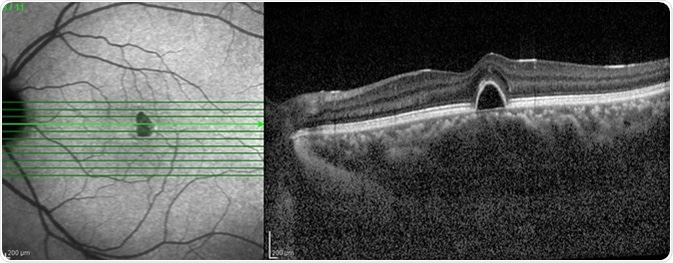

Optical Coherence Tomography (OCT) image of eye in the patient. Image Credit: Chaiwut Siriphithakwong / Shutterstock

OCT is a high-resolution optical imaging technique that is based on the interference between the signal from the object being investigated (the sample) and a local reference signal. OCT can produce a cross-sectional image of an object in real time. For OCT, the axial resolution of the image is dependent on the optical source, which is an advantage when compared to other methods such as confocal microscopy. OCT can be used to gain very high-resolution images of the retina even with optical aberrations and when narrow light beams are used.